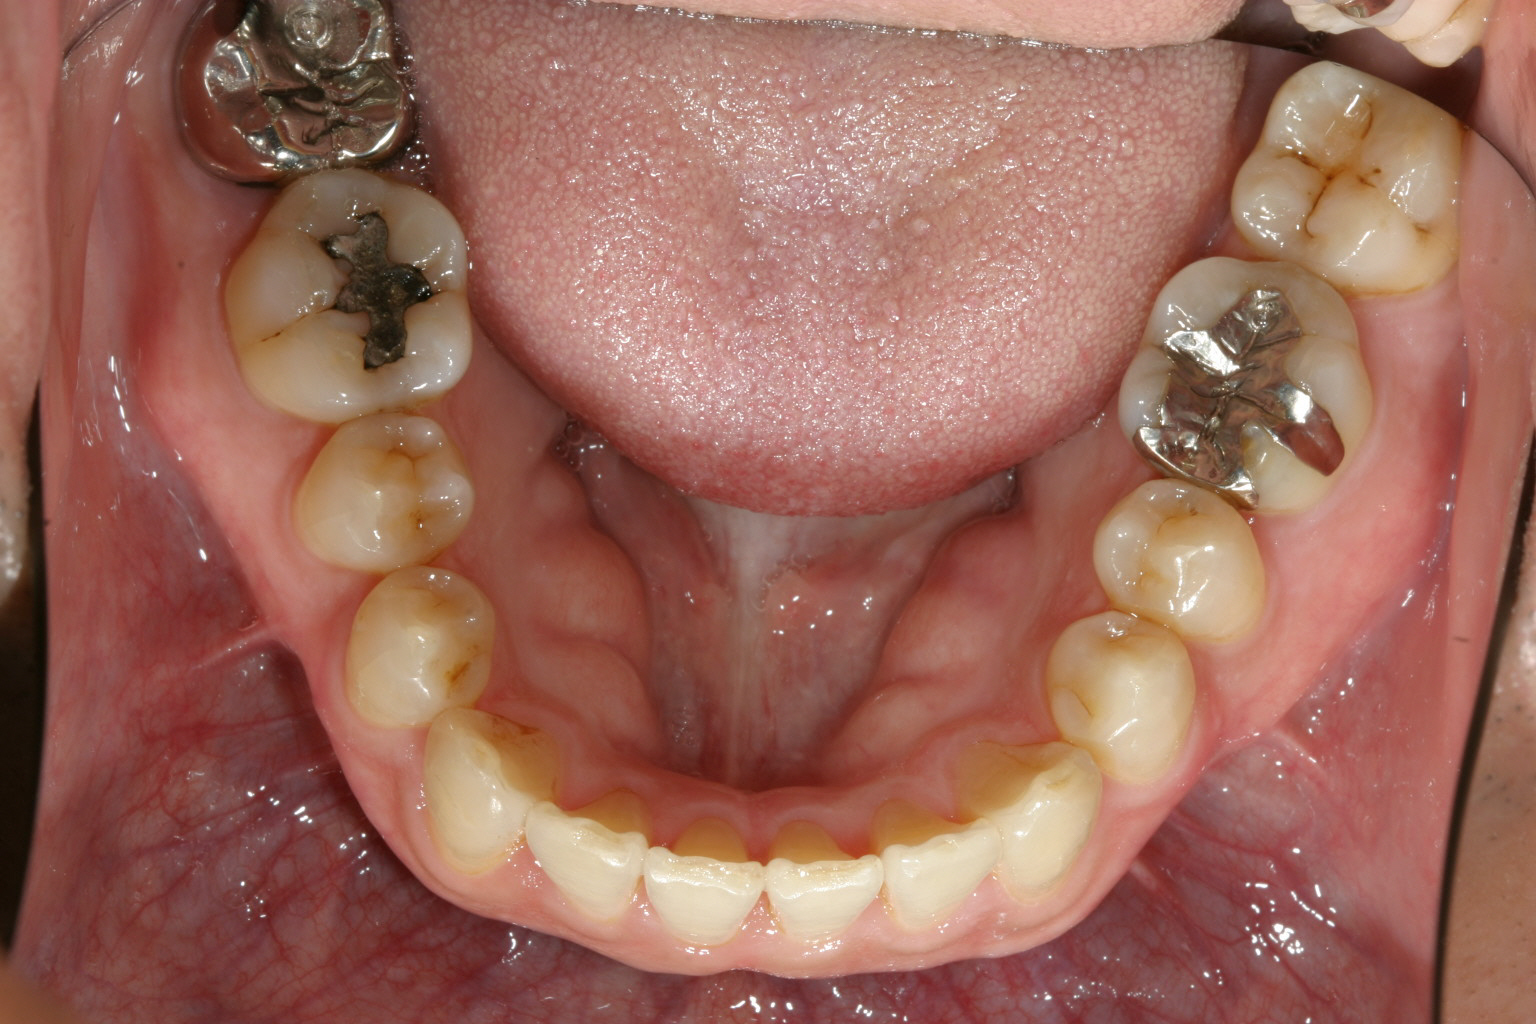

下顎も綺麗に整列しています。